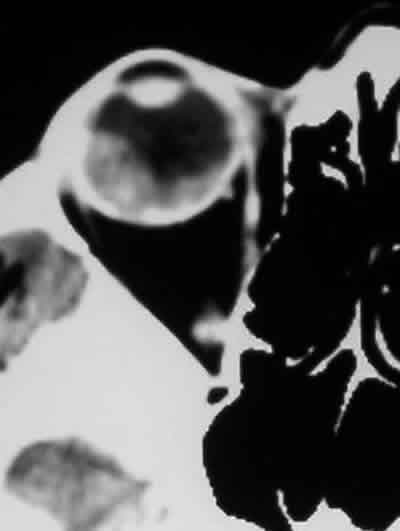

Otras pruebas diagnósticas como la angiografía fluoresceínica, la TC o la RNM raramente nos van a aportar información adicional (2) (figs 7 y 8).

Fig. 8. Secciones axiales de la TC y RNM orbitaria en la que se puede apreciar

la metástasis y el desprendimiento de retina asociados.